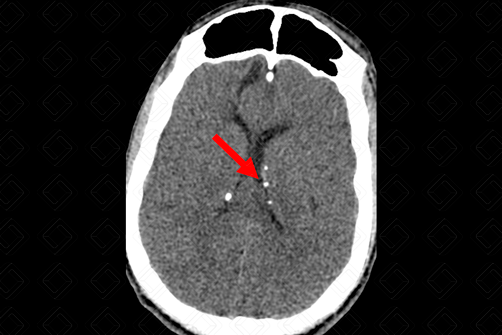

Texto alternativo para a imagem Figura 1. Créditos: Dra. Elazir Mota - Rio de Janeiro/RJ

Descrição das figuras 1 e 2: Tomografia computadorizada do crânio. Presença de nódulos subependimários calcificados – setas vermelhas (a calcificação deles permite a visualização na tomografia computadorizada). [cms-watermark]

• Nódulos subependimários: Representam hamartomas em crescimento e, comumente, são observados nesse grupo de pacientes. São lesões benignas, mas que podem degenerar para os astrocitomas de células gigantes. Caracterizam-se na tomografia de crânio em cerca de 88% dos casos e isso se deve ao fato da maioria deles serem calcificados nos estudos de imagem. Na ressonância apresentam sinal intermediário em T1 e iso a hipersinal em T2 (figuras 1 e 2);